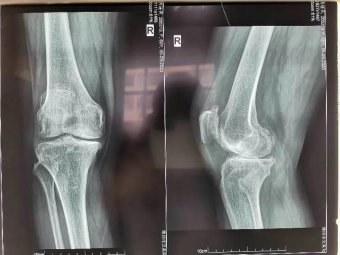

今年60歲的考大姨,飽受膝關節(jié)疼痛之苦長達8年,她曾四處求醫(yī),接受各種保守治療,至今跛行,且癥狀逐年加劇。近日因右膝疼痛加劇、腫脹,行走200米便無法繼續(xù)行走,嚴重影響日常生活,被親友急送濰坊市市立醫(yī)院治療。 骨二科主任許冬雷為患者做了詳細檢查,經(jīng)醫(yī)生…【查看詳細】

專于骨科,精于微創(chuàng)——骨二科近日完成一例膝關

近日,濰坊市市立醫(yī)院骨二科為50歲的徐先生行右膝關節(jié)骨關節(jié)炎單髁關節(jié)置換術。患者術后恢…【查看詳細】

專于骨科,精于微創(chuàng)——骨二科近日完成一例膝關節(jié)骨性關節(jié)炎單髁關節(jié)置換手術

生命走向健康的音符——骨二科為老人成功實施全膝關節(jié)置換術

嗒嗒 在骨科病房走廊,時常能聽到病人術后借助助行器行走特有的聲音,這是生命走向健康的音符。護士長,今天我感覺比昨天又好了一大截了。右腿吧,沒有什么感覺了;左腿呢,也敢著地了,走路也不怎么疼了69歲的姜大爺路過護士站熱情地跟醫(yī)護人員打招呼。原來,姜大爺兩個膝關節(jié)…【查看詳細】